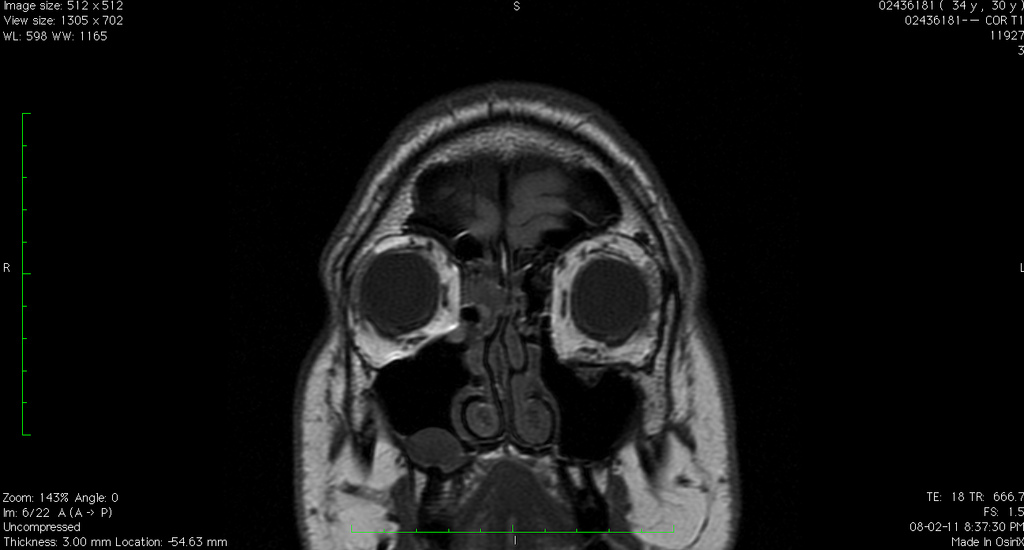

The first order of business for me was obtaining that final MRI on CD so I could take a close look at it. So a few weeks ago I went down to Vancouver General Hospital, paid $60, and left with my data on CD. I fired up the viewer on my laptop, and got the first real glimpse (other than an over-the-shoulder glance) of what my eye looks like on the inside. And here it is:

What should be obvious to most people, as it was obvious to me, is that the shape of my left eye isn’t really much better than how it was after my first surgery. This is what I thought I saw over the shoulder of the second surgeon, and ultimately confirmed a few weeks ago when I picked up the CD from VGH.